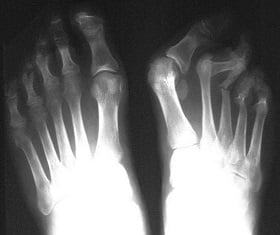

Могут наблюдаться полиартриты или асимметричные олигоартриты, которые преимущественно поражают пальцы стопы или крупные суставы нижних конечностей. При тяжелом течении заболевания возможны болевые ощущения в спине.

На фото можно рассмотреть внешние симптомы болезни, а вот в остальном следует обратиться к врачу, если имеются следующие жалобы: